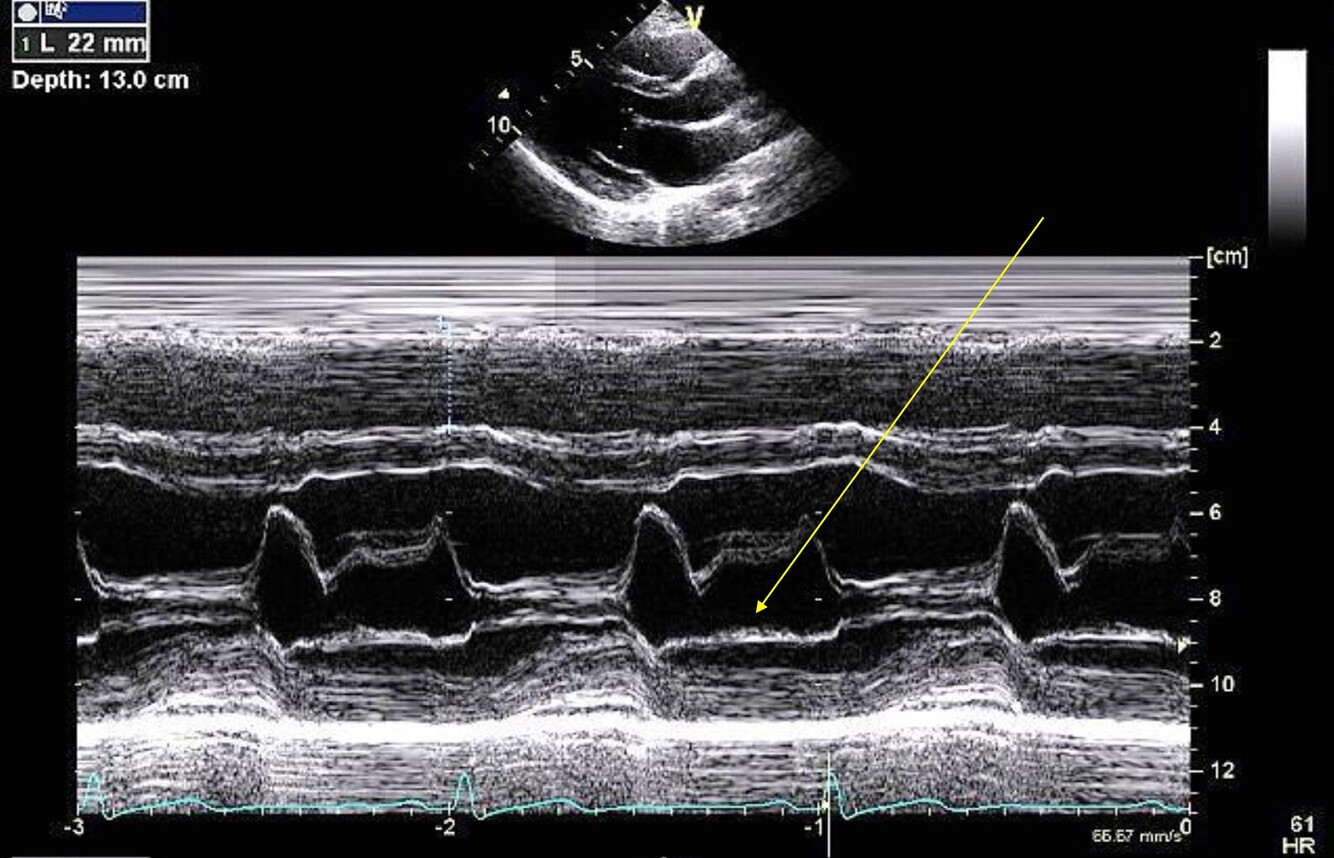

Label the picture

A

1. LA Filing

2. LA Emptying

3. Conduit phase

4. Rapid phase

5. Atrial systolic phase

Q

Label the structures of AV/LA M-mode

1. Anterior Ao Root

2. RCC AV cusp

3. NCC AV cusp

4. Posterior Ao root

5. LA

6. AV Closure line